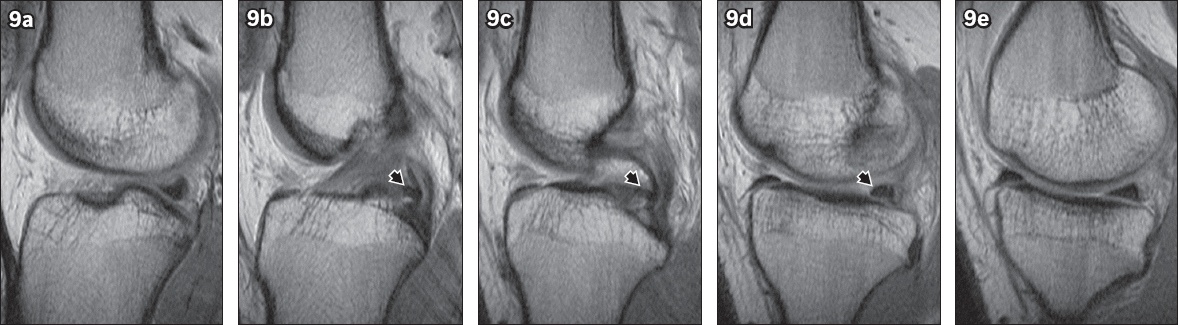

Fig. 9

Serial sagittal PD-weighted FSE MR images from the lateral to medial aspect of the knee show the course of the posterior intermeniscal ligament (arrowhead in 9b–d) as it attaches to the posterior horns of the medial and lateral menisci. Increased signal intensity at the interface between the ligament and posterior horn of the lateral meniscus mimics a tear (9d). The ligament can also be misinterpreted as a displaced meniscal fragment (9c).